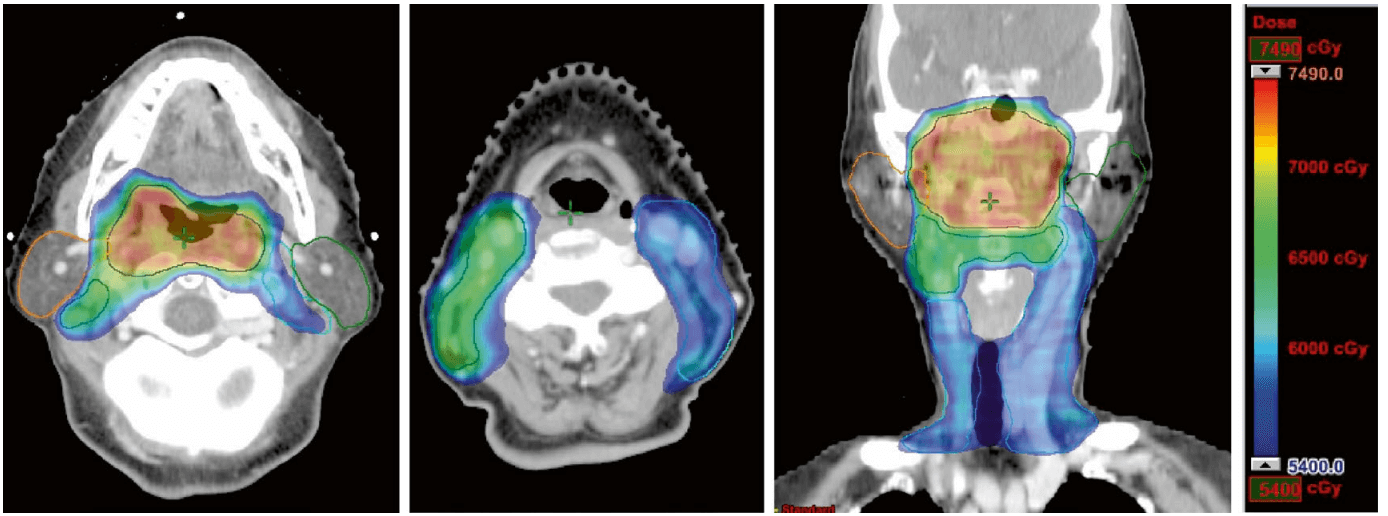

強度変調放射線療法 (IMRT) は、NPC に対する一般的な放射線療法です。

これには、人の周りを動く機械が含まれており、技師はさまざまな角度から X 線ビームを腫瘍に向けることができます。近くの組織やその他の構造が放射線の影響を受けないよう、ビームの線量と強度を調整できます。

このアプローチの利点は、副作用を軽減しながら、より高線量の放射線を腫瘍に照射できることです。